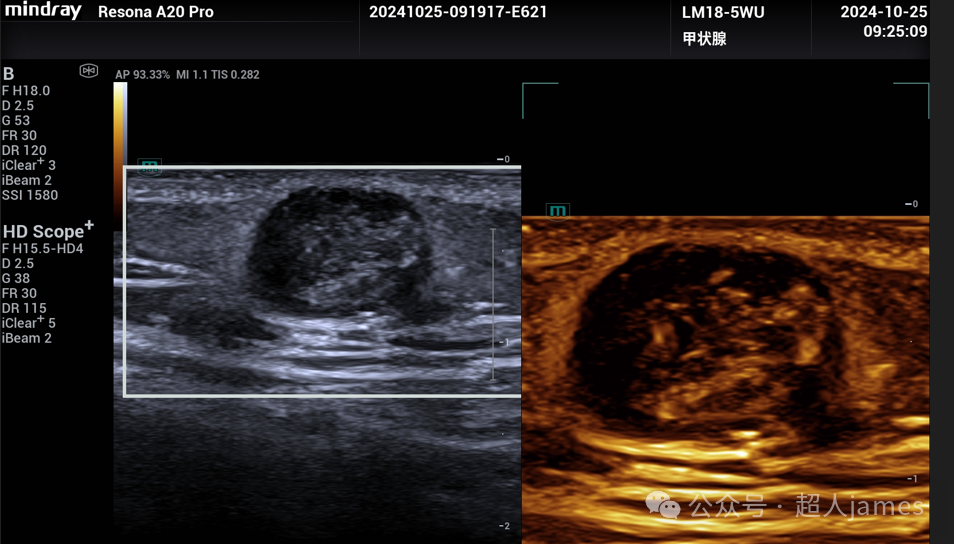

毛姆质瘤,又称钙化性上皮瘤,因此,其最大的特征就是在超声图像上往往表现为皮下以钙化为特征的包块。毛姆质瘤是来源于毛囊毛基质细胞的良性肿瘤,各年龄都可能发生,更常发生在儿童和青少年,单发多见,但也可以多发,常发生于头颈部。

超声表现多样,可以表现为实质片状钙化型、点状钙化灶型、无钙化型、完全钙化型等,边界清晰,后方衰减。利用UMA超微血流成像显示:实质区域可以探及血流信号,这一点是与皮脂腺囊肿、表皮样囊肿的重要鉴别点。